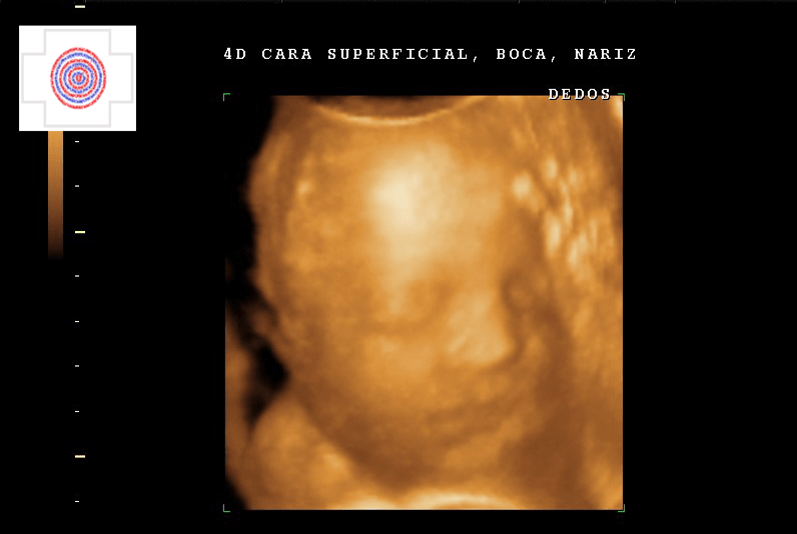

4D CARA SUPERFICIAL, BOCA, NARIZ, DEDOS